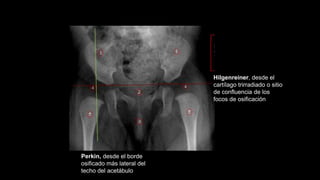

Hilgenreiner, («Y»)

desde el cartílago

trirradiado o sitio de

confluencia de los focos

de osificación

Perkin, desde el borde

osificado más lateral del

techo del acetábulo

Hilgenreiner, desde el

cartílago trirradiado o sitio

de confluencia de los

focos de osificación